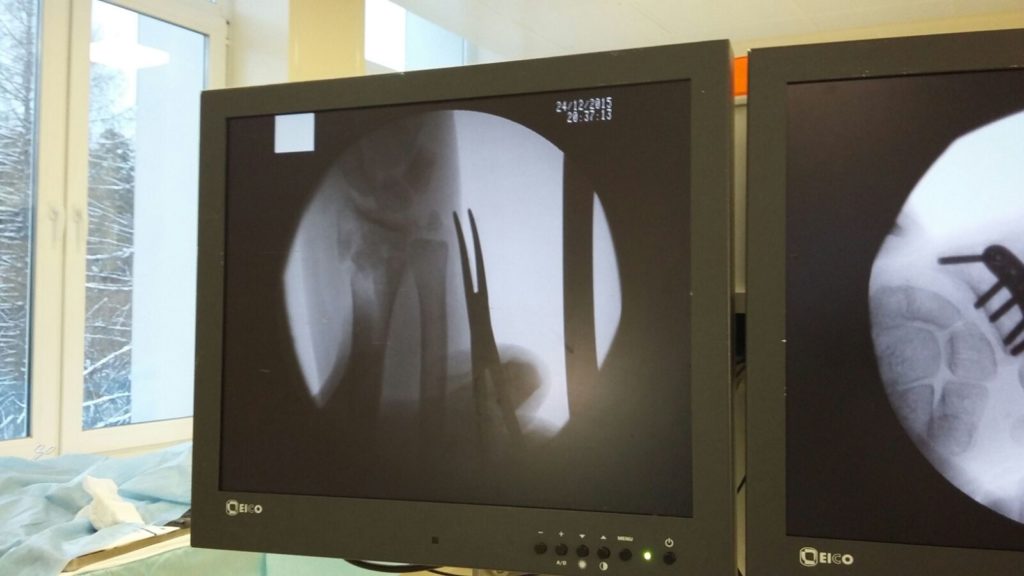

Операция - открытая репозиция, остеосинтез лучевой кости пластиной с костной ксенопластикой материалом "Остеоматрикс". На контрольных снимках в три месяца имеется консолидация перелома, миграции фиксатора нет, имеется остеоинтеграция ксенопластического материала.